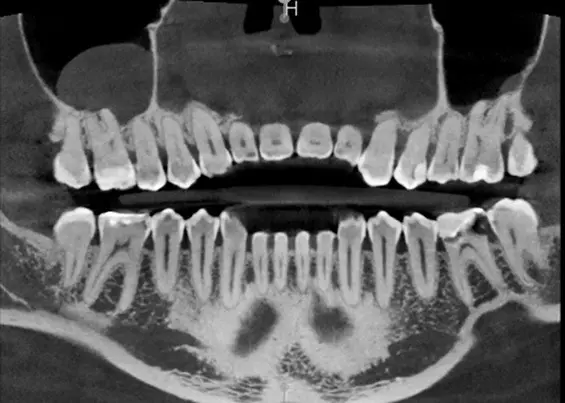

W tym wydaniu m.in: koferdam w adhezyjnych protokołach rekonstrukcyjnych, Low Dose – przełom w tomografii komputerowej CBCT, odpowiedzialność karna lekarza za błąd medyczny, wykorzystanie sonoabrazji w różnych dziedzinach stomatologii.

W majowym wydaniu czasopisma Stomatologia Practise&Cases poruszamy temat sztucznej inteligencji w stomatologii. Największe i najgłębsze zmiany w stomatologii postępują równocześnie z rozwojem sztucznej inteligencji w tej dziedzinie. Nowoczesne urządzenia dentystyczne są wyposażone w oprogramowanie z SI. Każdego roku programy te są modyfikowane lub powstają nowe, co zmienia i ułatwia pracę stomatologów. Należy pamiętać, że proces ten jest bardzo dynamiczny. W jakich dziedzinach stomatologii stosuje się sztuczną inteligencję? Jakie zagrożenia niesie za sobą rozwój SI w stomatologii? Zapraszamy do lektury!